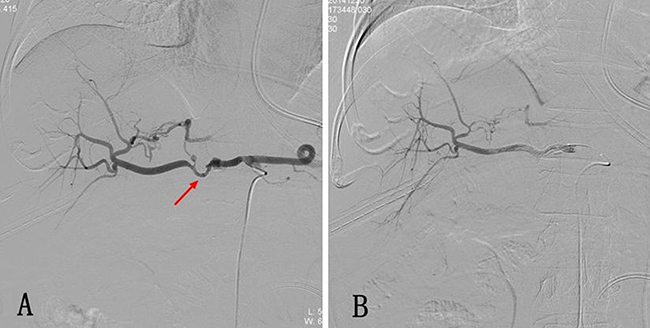

All DSA procedures were technically successful, and initial hemostasis was achieved in 29 patients. Of the 29 patients, pseudoaneurysm alone was observed in one patient (3.4%), pseudoaneurysm and active extravasation in two (6.9%), active extravasation in 22 (75.9%), and luminal irregularity in four (13.8%). The hemorrhagic focus in the angiograms was observed in the gastroduodenal artery (GDA) stump in 11 patients, in the hepatic artery in 13, in the superior mesenteric artery in two, in the left gastric artery in two (Figure 2), and in the splenic artery in one. A pushable coil (selective artery embolization) was used as the embolizing agent in 15 patients, and a covered stent was used for one patient (Figure 1). Embolization was established with a pushable coil along with PVA in three cases, a pushable coil along with a gelatin sponge particle in five cases, and a gelatin sponge particle alone in five cases. Recurrent bleeding occurred in eight of the 29 patients (27.6%) after the first endovascular treatment. A repeat procedure was performed in five patients, though the bleeding sites were not discovered, and three patients underwent a laparotomy following endovascular procedures for a washout of a massive hemoperitoneum performed at the discretion of the surgical team (Table 2). Five of the 13 patients with a negative DSA examination changed to symptomatic supportive treatment, and the other eight patients were evaluated using an endoscopy (n = 4, 1 with capsule endoscopy) and a laparotomy (n = 4) to identify the source of hemorrhage. No procedure-related complication developed in any other case. No rebleeding in a late stage occurred in the other cases. Mortality occurred in five (17.2 %) of the 29 patients: two died from severe infections and three from multiple organ failure.

Figure 1: (A) Postoperative hemorrhage after Whipple operation. The selective celiac artery arteriography shows the bulging of the proximal end of the common hepatic artery, while the distal end of the artery remains slender. Local overflow of the contrast agent is also displayed (arrow). (B) Arteriography was performed again after a 5 mm* 5 cm covered stent was implanted through the vessel lumen, and it shows that the sign of contrast agent overflow disappeared.